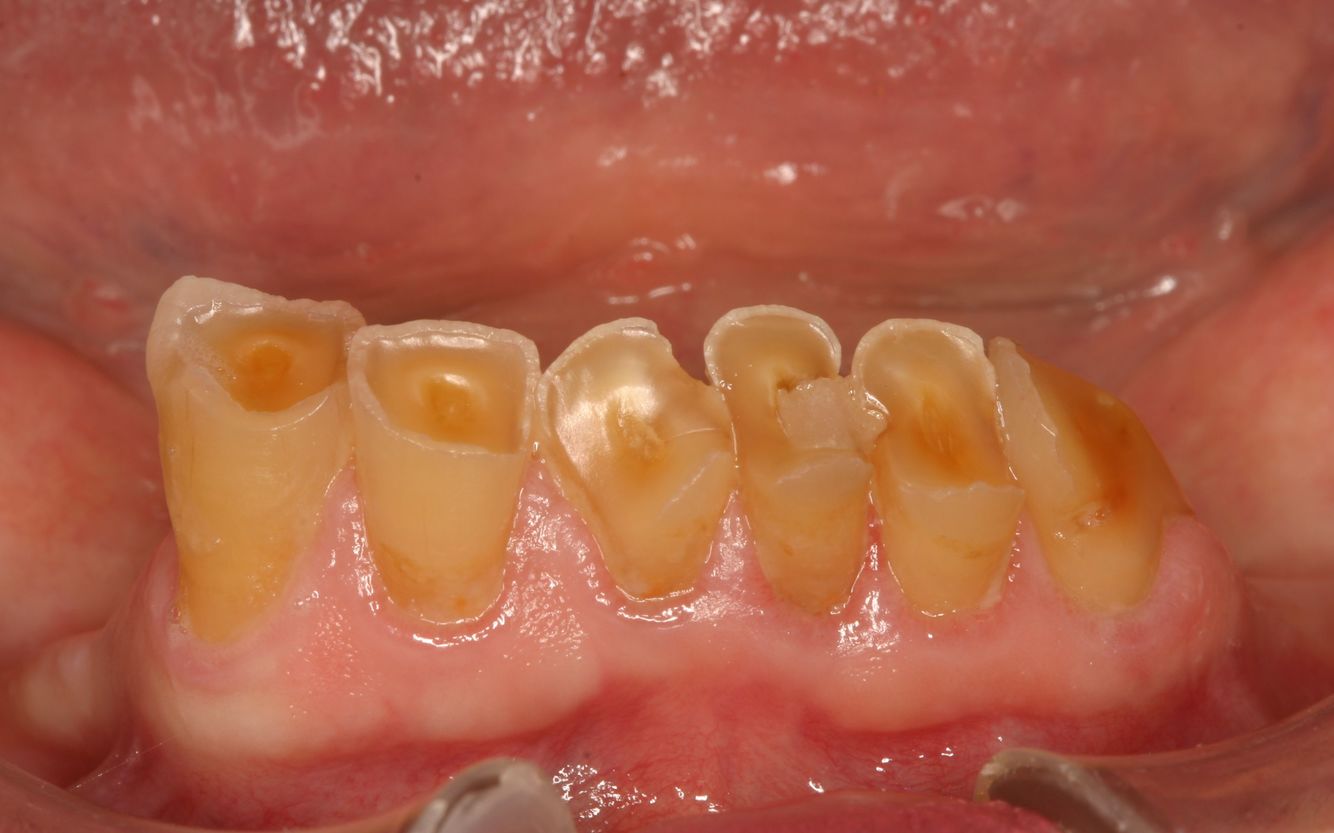

What kind of post-developmental loss of tooth structure is this?

Attrition *caused by bruxism*